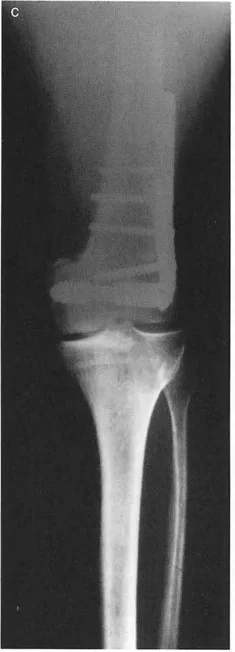

Correcting Valgus Deformity with Varus Osteotomy

Consider a severe valgus deformity of the proximal femur with a preoperative LPFA of 75 degrees (normal LPFA is roughly 90 degrees). To correct this limb to a normal mechanical alignment and restore hip biomechanics, a varus-producing osteotomy is required.

When a standard 90-degree angled blade plate is applied to this valgus femur, the geometry of the plate automatically dictates the correction. If the blade is inserted into the femoral neck parallel to the neck axis, the side plate will sit at a 90-degree angle to the neck.

When the femoral shaft is brought laterally to meet the side plate, the LPFA is automatically corrected from 75 degrees to 90 degrees. However, because the osteotomy is performed below the CORA (which is typically in the femoral head or neck), this represents a Rule 2 osteotomy. The 90-degree plate automatically forces an angulation and a lateral translation of the femoral shaft.

If the surgeon fails to anticipate this lateral translation, the mechanical axis will be shifted laterally, potentially creating a secondary valgus MAD at the knee. To prevent this, the surgeon must calculate the exact amount of translation required and ensure the hardware accommodates it without shifting the overall mechanical axis.